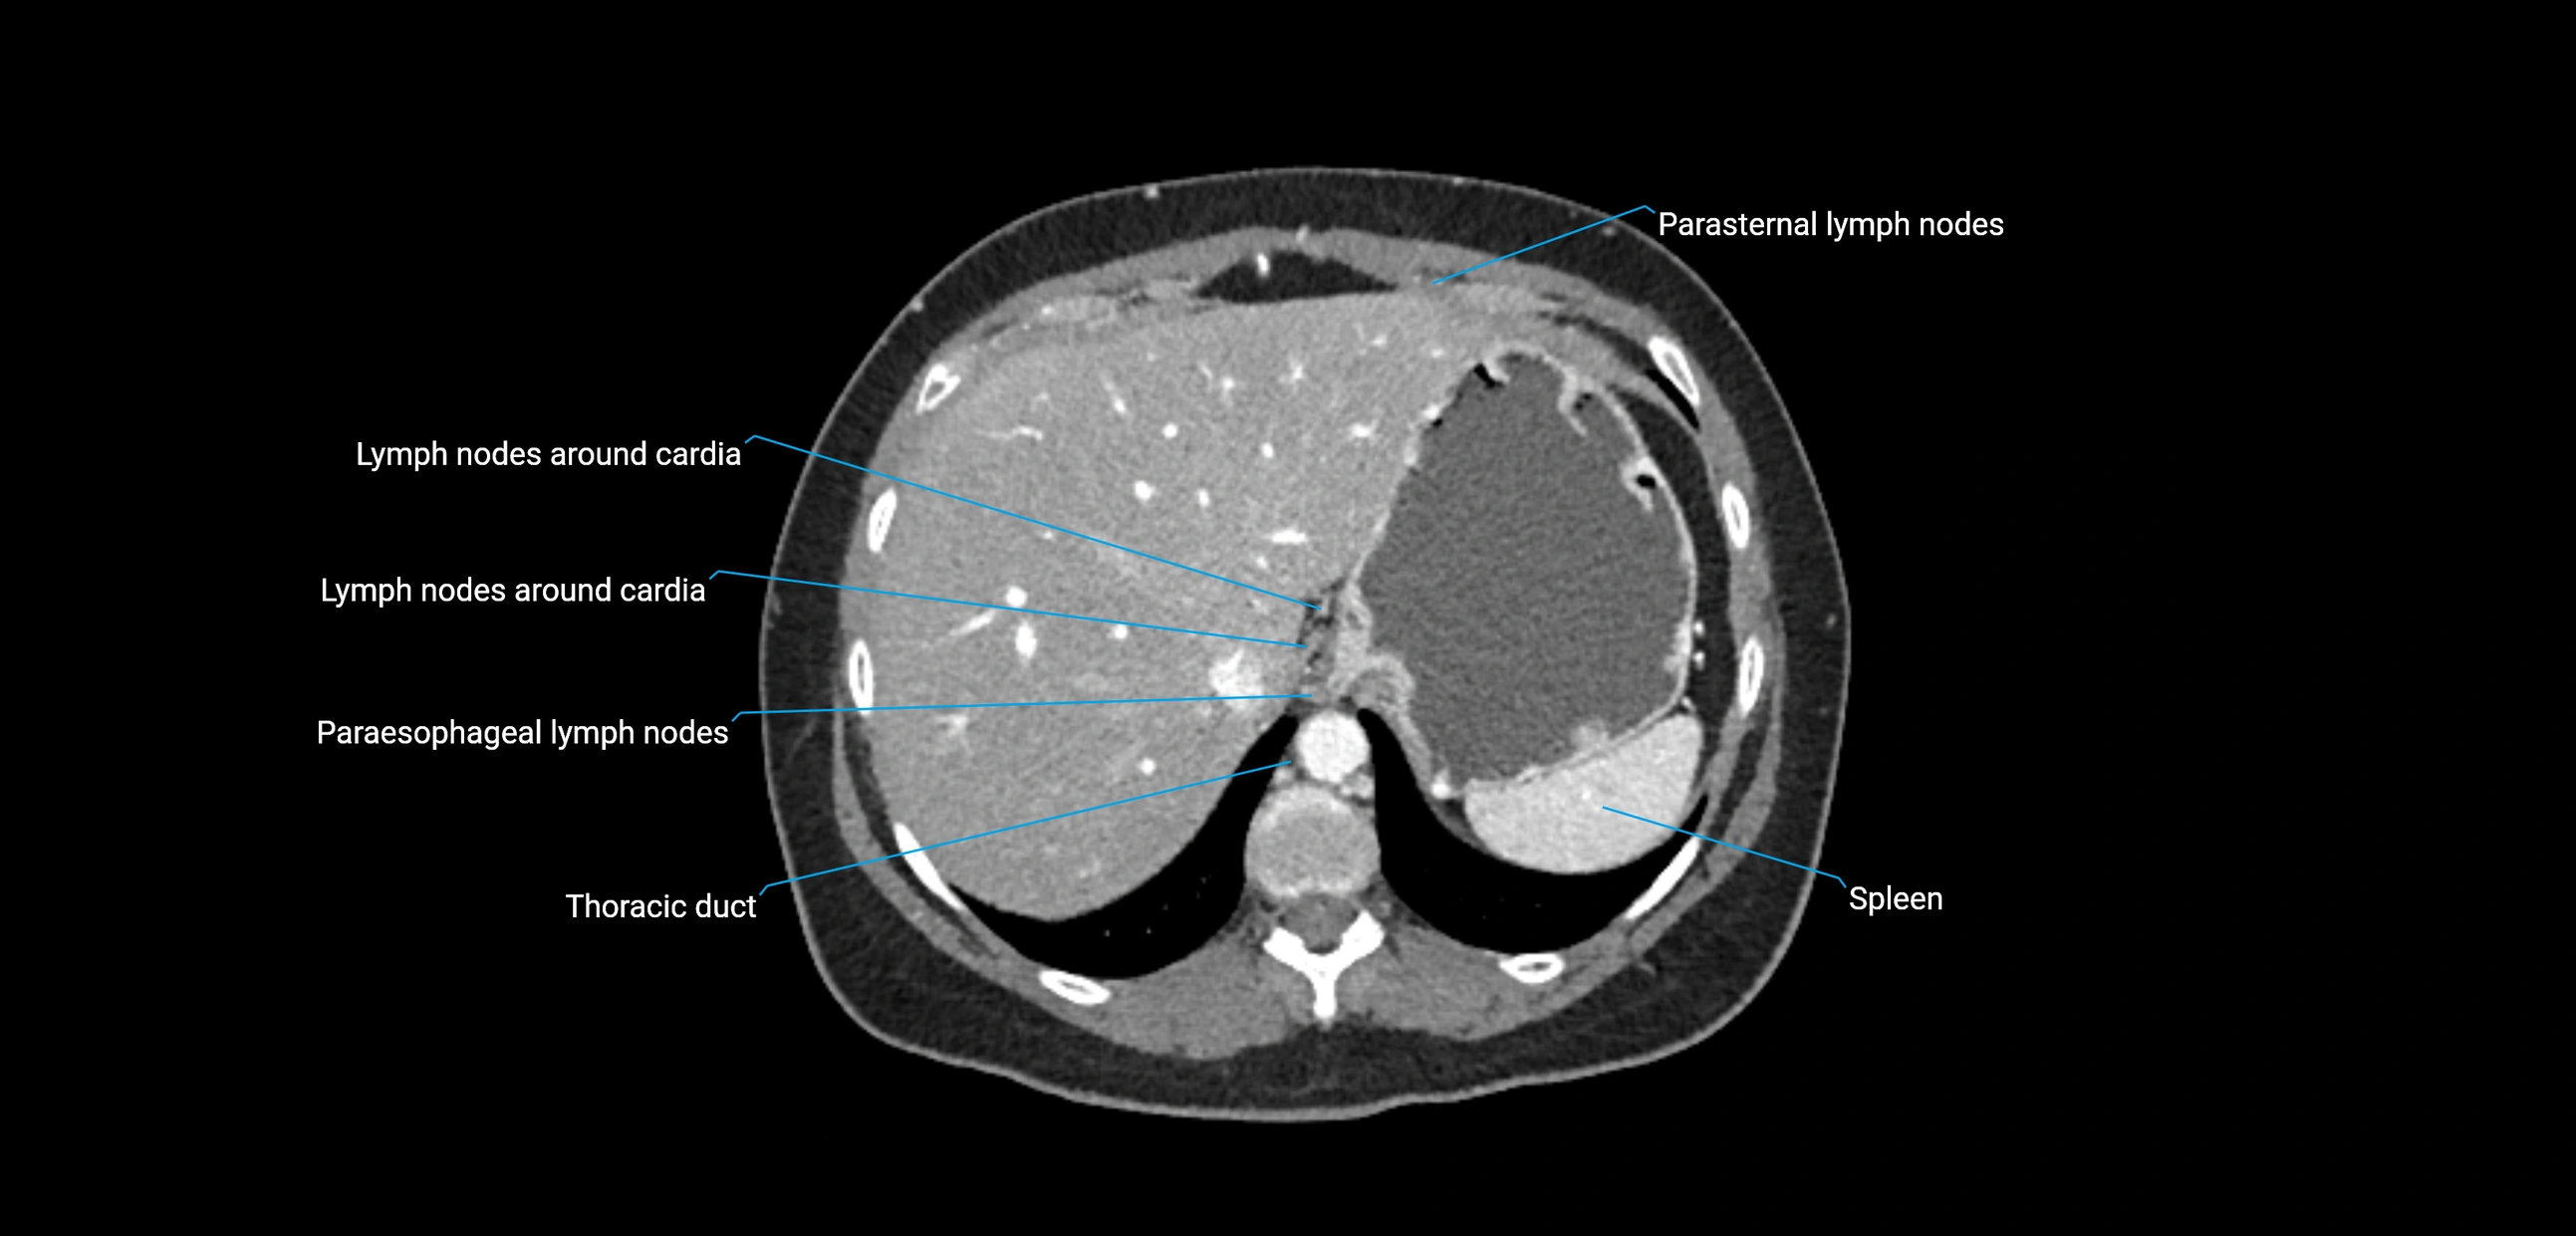

CT Appearance

CT Post-Contrast:

• Normal nodes enhance homogeneously

• Malignant nodes may show heterogeneous enhancement, central necrosis, or conglomerate formation

• Size >1 cm short axis is suspicious, though morphology and distribution are equally important